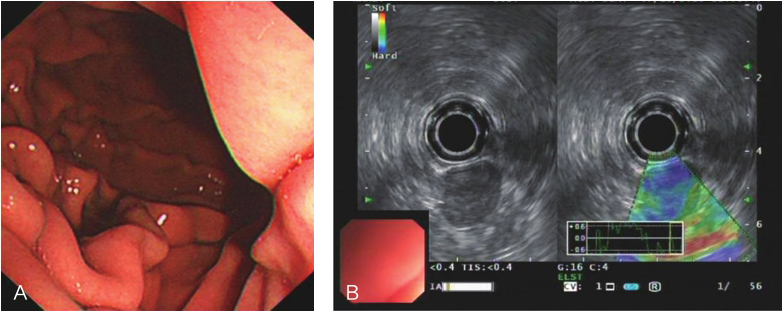

电子超声胃镜:胃体后壁见一扁平隆起,表面光滑;胃体病灶处见一类圆形低回声病灶,凸向腔外生长,边界清楚,内部回声均质,最大切面1.5cm×1.6cm,起源于固有肌层深层,周边未见肿大淋巴结,超声弹力成像质硬(图2)。

图2 超声胃镜提示胃体低回声病灶,最大切面约1.5cm×1.6cm

A.胃镜;B.超声内镜